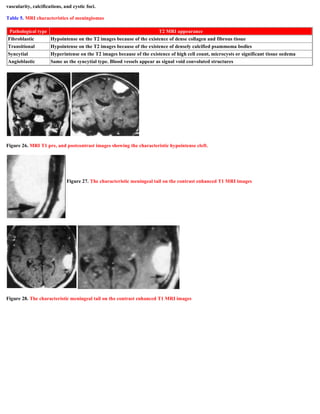

Table 5. MRI characteristics of meningiomas

Figure 26. MRI T1 pre, and postcontrast images showing the characteristic hypointense cleft.

Pathological type T2 MRI appearance

Fibroblastic Hypointense on the T2 images because of the existence of dense collagen and fibrous tissue

Transitional Hypointense on the T2 images because of the existence of densely calcified psammoma bodies

Syncytial Hyperintense on the T2 images because of the existence of high cell count, microcysts or significant tissue oedema

Angioblastic Same as the syncytial type. Blood vessels appear as signal void convoluted structures